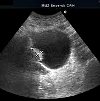

УЗИ мочевого пузыря

УЗИ мочевого пузыря показано при подозрении на воспаление, камни, мусор, дивертикулы или новообразования для изучения проходимости мочеточников. Для обследования вам понадобится наполненный мочевой пузырь. Поэтому пациенту не нужно мочиться ни за 5 часов до обследования, ни пить 1 литр воды без газа за 1-1,5 часа до УЗИ. Обследование мочевого пузыря происходит в положении лежа через переднюю стенку живота. Существует возможность исследования через стенку прямой кишки, где в анус вводится ультразвуковой преобразователь.

Ультразвук мочевого пузыря представляет собой сканирование мочевого пузыря с акустическими волнами, распространяющимися во время ультразвукового излучения. В арсенале диагностики, применяемом в клинической урологии, есть трансабдоминальный, трансвагинальный, трансуретральный или трансректальный метод проведения УЗИ мочевого пузыря.

Наиболее часто выполняется УЗИ мочевого пузыря через нижнюю брюшную стенку. Трансректальное УЗИ мочевого пузыря с датчиком, размещенным в прямой кишке, обычно используется при обследовании мужчин. Трансвагинальное УЗИ мочевого пузыря у женщин проводится через влагалище. При ультразвуковом исследовании трансуретрального мочевого пузыря датчик вводится в уретру. При необходимости трансуретральное, трансвагинальное и трансректальное УЗИ мочевого пузыря используется для определения основных повреждений, обнаруженных при обследовании брюшной полости.

УЗИ мочевого пузыря может предоставить урологу ценную информацию, которая дополняет цистоскопию, урографию, компьютерную томографию. УЗИ мочевого пузыря, в отличие от восходящей цистографии, обычно не требует катетеризации и введения жидкости в мочевой пузырь.